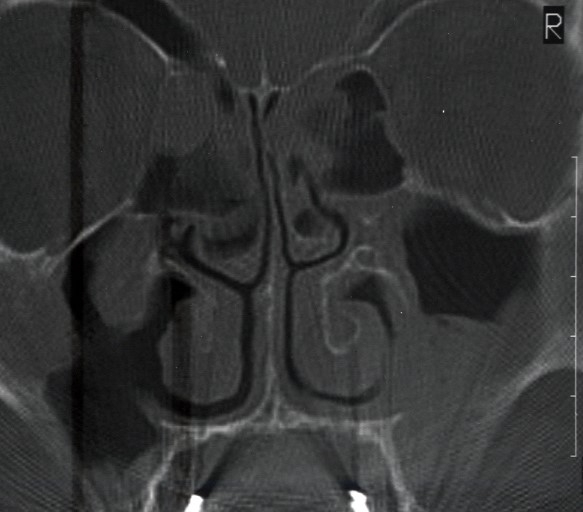

Bazı durumlarda yapısal nedenlerle, bazı durumlarda ise rinite yol açan nedenlerle alt konkalar (alt burun etleri) normalin üzerinde büyüme gösterir. Yapısal nedenler arasında en sık görüleni doğuştan ya da daha sonradan karşılaşılan travmalara bağlı burun septumunun deviye olmasıdır (septum deviasyonu). Septum deviasyonuna bağlı olarak daha geniş kalan burun boşluğundaki alt konka, dışarıdan alınan solunum havasına direnç oluşturabilmek, onu ısıtabilmek ve filtre edebilmek için büyür.

Burun eti büyümesinin en sık birlikte görüldüğü durum septum deviasyonu yani burun orta duvarında kıkırdak ve/veya kemiğin eğriliğidir.

Alt burun etlerini küçültmek için günümüzde en koruyucu ve en etkili yöntem koblasyon ve radyofrekans gibi yüksek teknolojik aletlerle konkaların küçültülmesidir. Orta burun etleri bazı hastalarda içerisinde sinüs benseri bir hava boşluğu içerir. Büyümüş orta konka hava yolunu tıkar. Bu duruma konka bullosa adı verilir. Bu durumda, orta konkalar işlevsel iç yüzleri korunarak klasik cerrahi yöntemlerle küçültülür. Her iki grup ameliyat endoskopik olarak (burun içerisinin işlem esnasında kamera ile görüntülenmesi ile) çok kısa sürede ve başarı ile uygulanabilir. Burun kemiğinde eğrilik olan hastalarda aynı seansta septoplasti yapılması da bir gerekliliktir. Burun eğriliği var iken sadece burun etini küçültülmesi fizyolojinin istenen şekilde düzelmesine izin vermez. Fonksiyonel ve estetik cerrahiler, sinüzit ameliyatları gibi buruna yönelik her türlü cerrahi girişimde konka müdahalesi de yapılabilir.